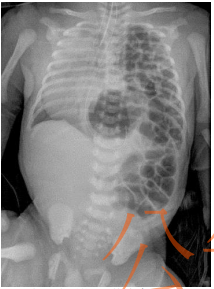

38. 一位新生兒,出生後因呼吸窘迫而插管使用呼吸器,X光片顯示如下圖。下列診斷何者 最有可能? (A) 先天性橫膈膜疝氣( congenital diaphragmatic hernia ) (B) 張力性氣胸(tension pneumothorax ) (C) 大動脈轉位症(transposition of great arteries) (D) 食道閉鎖併下段食道氣管瘻管( esophageal atresia with tracheoesophageal fistula )